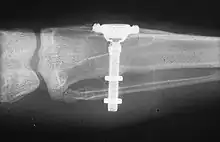

The design of implants has to account for a lifetime of real-world use in a person's mouth. Regulators and the dental implant industry have created a series of tests to determine the long-term mechanical reliability of implants in a person's mouth where the implant is struck repeatedly with increasing forces (similar in magnitude to biting) until it fails.[31]